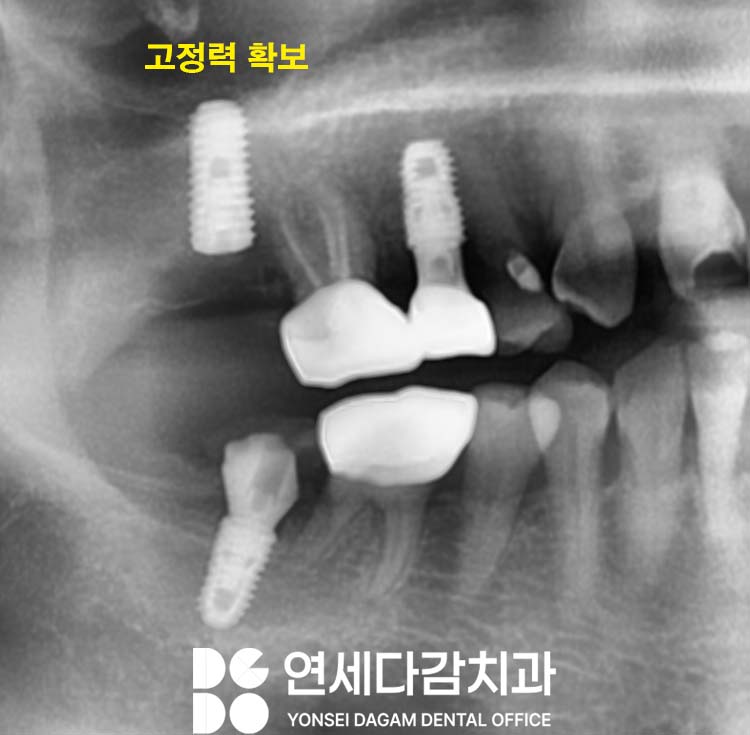

결과

이와 동시에 일반적으로 사용되는

길이보다 더 긴 고정체를 선택하여,

근단부(끝부분)가 상악동 저의

피질골에 닿도록 시행했습니다.

이를 통해 상악동 저의

단단한 피질골에서 고정력을

얻을 수 있었습니다.

상악동저 피질골을 활용한

접근법이 잘 적용됐음을

확인할 수 있었습니다.

이후 고정체와 주변

골조직이 골 유착되는 과정을

충분히 기다렸습니다.

골다공증으로 인해

일반적인 경우보다

더 신중한 관찰이 필요하여

과정이 오래 걸렸지만

안정적으로 치유되어

최종 보철물도 무사히 완성할 수 있었습니다.